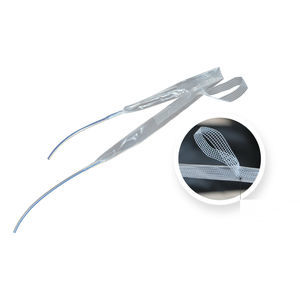

banda de reconstrucción para la incontinencia urinariaI-STOP

... Implante quirúrgico destinado al tratamiento de la incontinencia urinaria de esfuerzo en la mujer. Desarrollado en 2002 en colaboración con un grupo de especialistas e ingenieros, este dispositivo ha sido objeto de numerosos estudios clínicos. La ...

banda de reconstrucción para la incontinencia urinariaI-STOP

... desprende partículas. - Ligereza. - Punto macroporo. - Tipo 1: 100 % polipropileno monofilamento. - Agujas para técnicas retropúbica, suprapúbica, transobturatriz outside-in, transobturatriz inside-out. ...

banda de reconstrucción para la incontinencia urinariaB-FIX

... incontinencia urinaria de esfuerzo. El dispositivo puede implantarse tanto con el método transobturador (TOT) como con el método retrópubico (TVT). El ajuste puede realizarse hasta siete días después de la operación. La queja de incontinencia ...